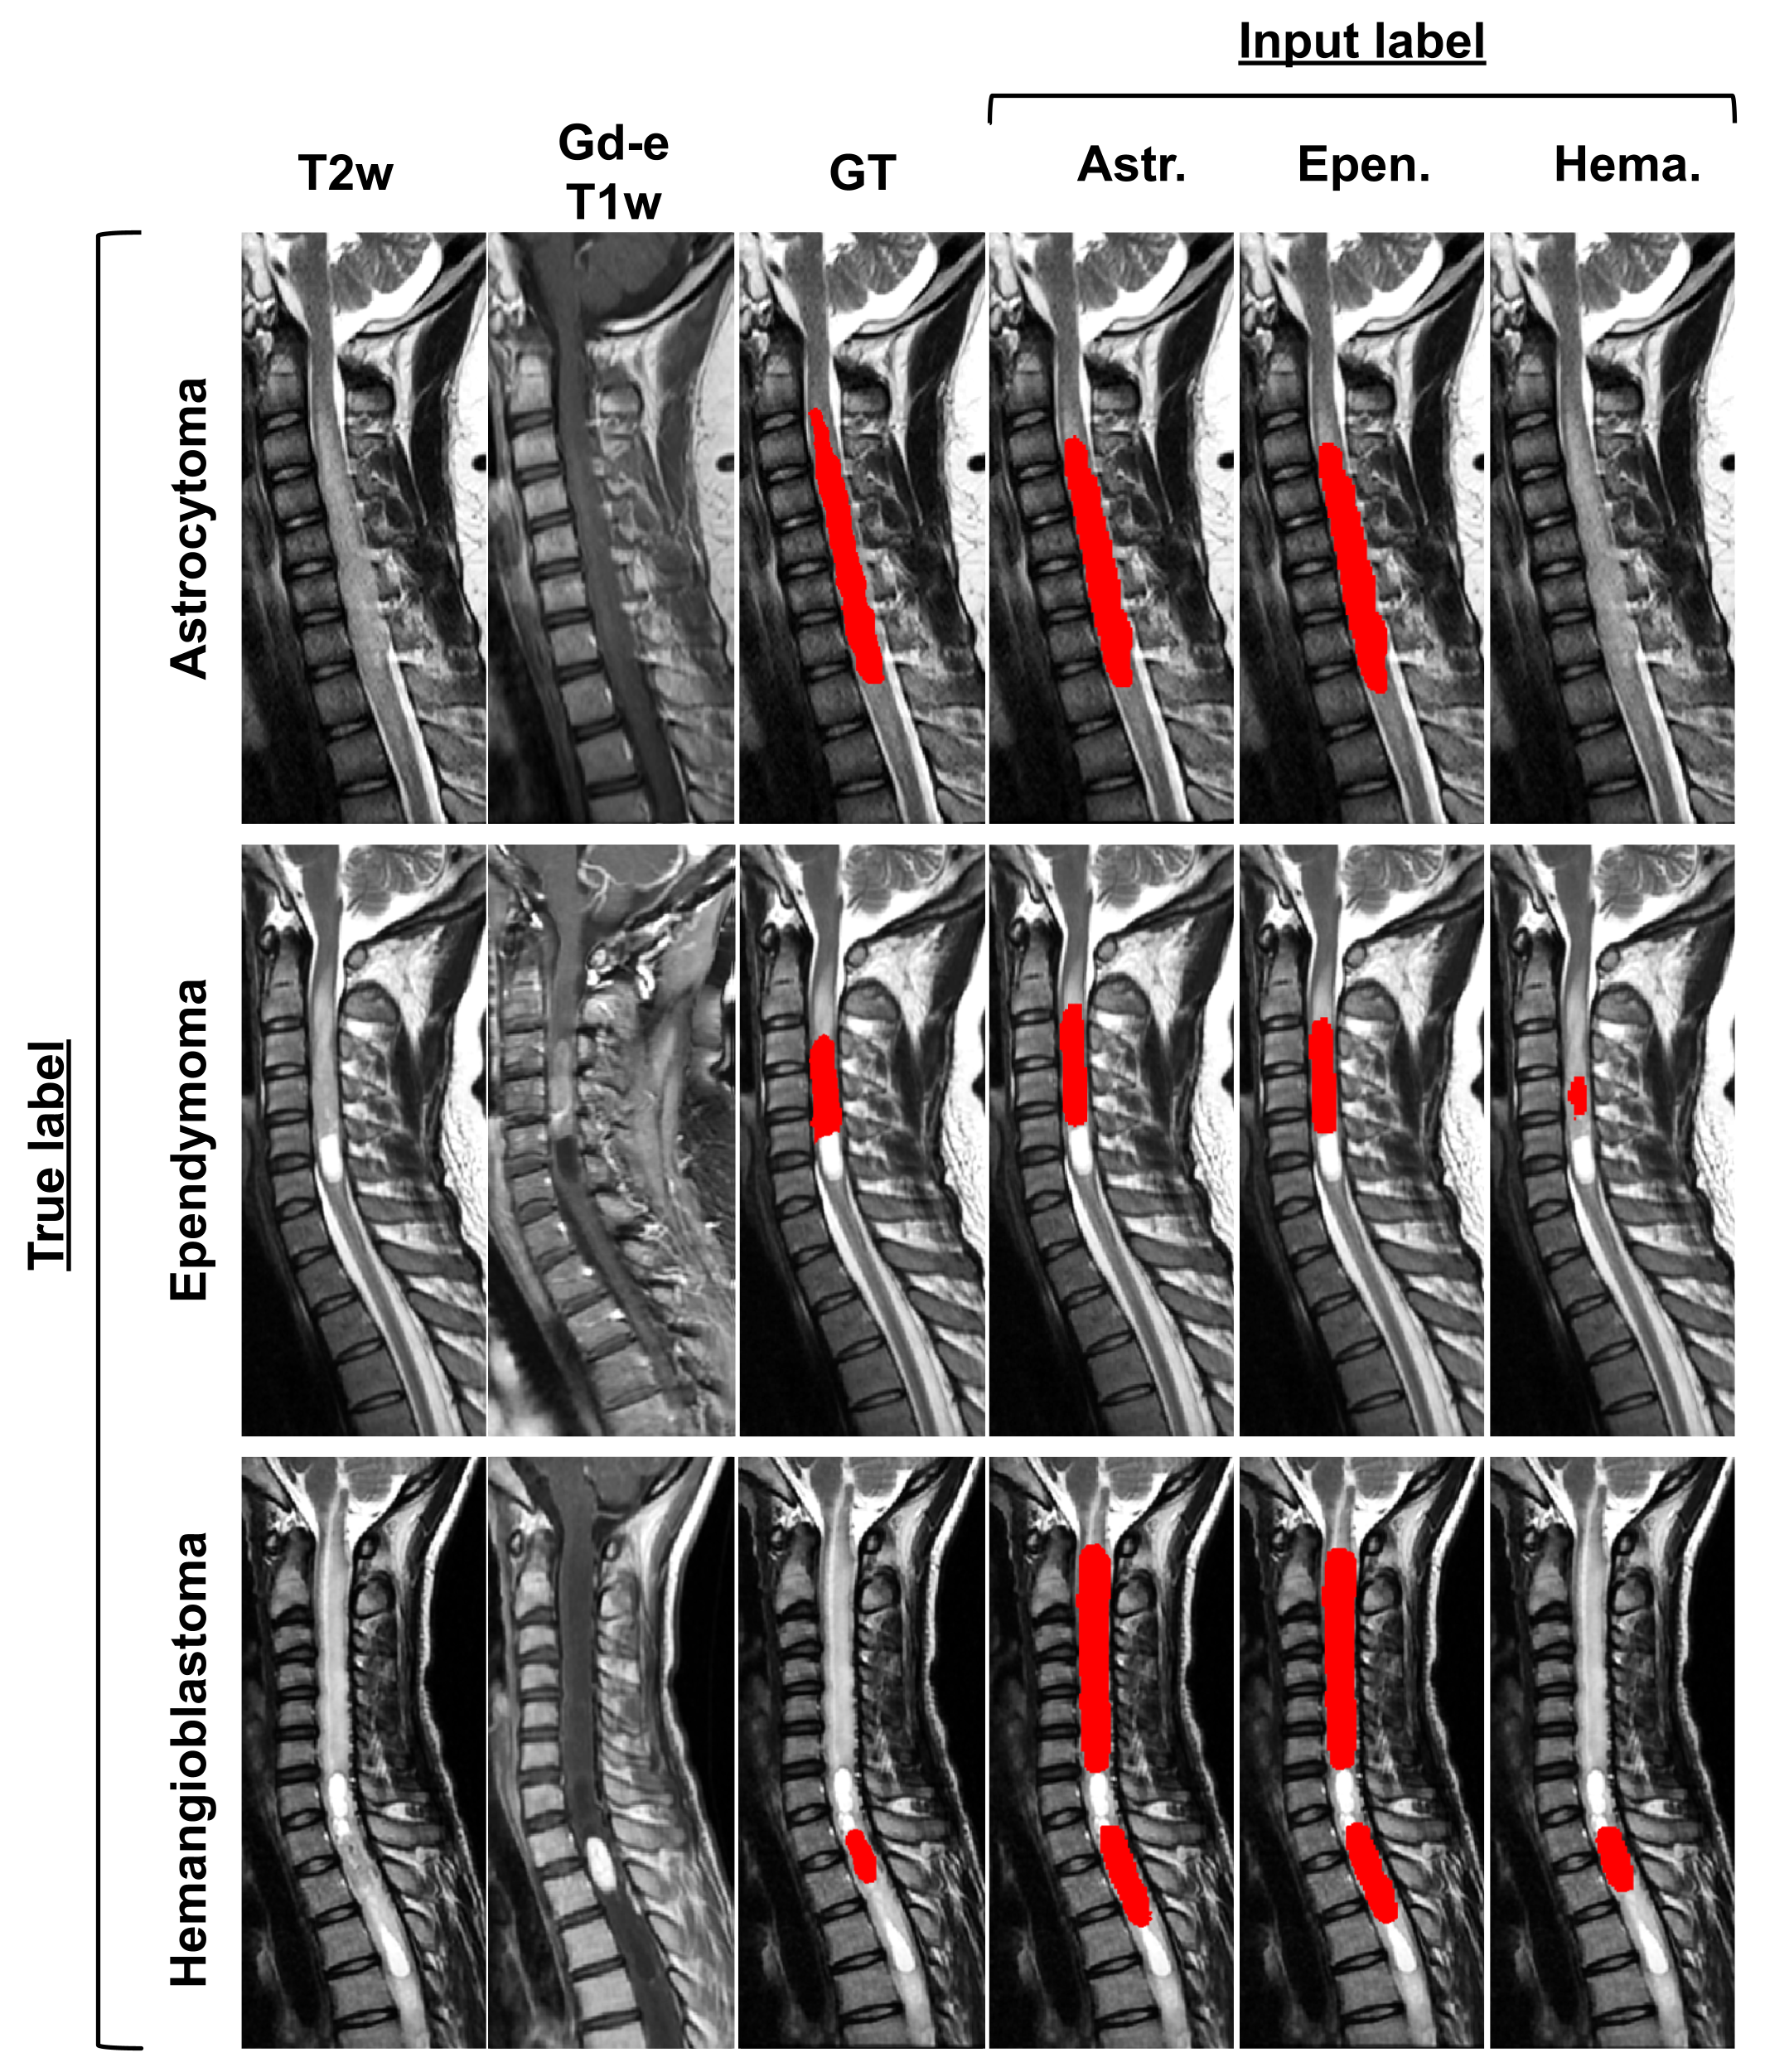

fig:Tumor

Astrocytomas are typically large, have ill-defined boundaries, and present heterogeneous, moderate, or partial enhanced in the Gd-e T1w contrast [Baleriaux(1999)]. Astrocytomas are usually extensive, expanding from 2 to 19 vertebral bodies in size [Baleriaux(1999)]. In both A1 and A2 predictions from the model without prior information, the segmented tumor size was one vertebral body or less and corresponded to the most enhanced tumor signal on the Gd-e T1w (ignoring the rest of the lesion).

In counterpart, hemangioblastomas are usually associated with a small tumor core [Baleriaux(1999)] intensely enhanced on Gd-e T1w [Baker et al.(2000)Baker, Moran, Wippold, Smirniotopoulos, Rodriguez, Meyers, and Siegal]. Figure LABEL:fig:Tumor H1 presents a hemangioblastoma barely apparent in T2w and hidden by the cavity (hyperintense signal). The small hyperintense signal on the Gd-e T1w contrast was overseen by the regular approach. On H2, the model oversegmented the tumor and identified a second tumor on a hypointense signal. The false positive tumor identification does not present an intense Gd-e T1w enhancement which is usually the case for hemangioblastomas. This false positive is not present for the model informed by the tumor type.

fig:Tumor_style

To assess the impact of inputting the tumor type, each prediction was modulated by the different tumor types. Table LABEL:tab:tumor_style presents the quantitative results for each condition while Figure LABEL:fig:Tumor_style qualitatively illustrates the impact of changing the tumor type. The highest Dice scores are reached when the input label corresponds to the true label. The modulation with FiLM successfully encoded knowledge about the tumor types and the predictions are in agreement with known characteristics of the different types. Astrocytoma and ependymoma yield similar predictions. Both tumor types have overlapping characteristics [Kim et al.(2014)Kim, Kim, Choi, Sohn, Yun, Kim, and Chang]: high intensity signals on T2w, comparable enhancement patterns, similar size (astrocytoma: 2-19 vertebral bodies, ependymoma: 2-13 vertebral bodies [Baleriaux(1999)]), etc. Predictions with hemangioblastoma as input diverge from the other tumor types. Hemangioblastoma predictions reflect their characteristics: small tumor cores intensely enhanced in Gd-e T1w, as seen in Figure LABEL:fig:Tumor. When inputting the hemangioblastoma label for the astrocytoma (first row of Figure LABEL:fig:Tumor_style) no prediction is given since the Gd-e T1w modality has moderate enhancement. Similarly, for the ependymoma, only the most Gd-enhanced portion of the tumor is predicted when assigning the hemangioblastoma label with FiLM (second row of Figure LABEL:fig:Tumor_style). The results from Table LABEL:tab:tumor_style and Figure LABEL:fig:Tumor - LABEL:fig:Tumor_style confirm that FiLM layers are able to learn characteristics from the metadata that are relevant for the segmentation.